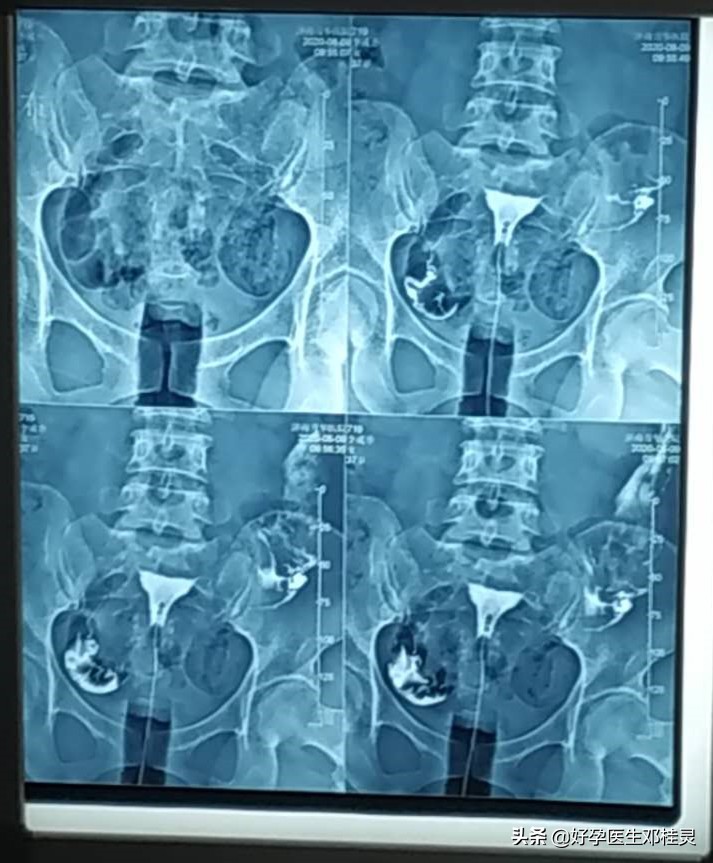

子宫输卵管造影是通过导管向子宫和输卵管注入造影剂,通过X线来透视和摄片,然后根据造影剂在输卵管和盆腔内的造影情况分析输卵管通畅程度、阻塞的部位和宫腔的情况,是临床上很多不孕症女性常做的检查之一。

正常的子宫输卵管造影,应该是很容易就能把造影剂推进去,而且患者不会出现疼痛等明显症状。现在临床上的造影剂选用的都是碘水,常用76%的泛影葡胺,渗透压低,粘稠度低,可以扩散到输卵管的分泌物中,15分钟就能完成摄片,减少X线照射时间,注入半小时以内就能被身体吸收,对女性身体伤害小。